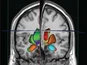

Beyond traditional post-mortem analyses (histology, morphometry, pathophysiological and biochemical markers), non-invasive in vivo imaging techniques are playing an increasingly important role. Prisys Biotech offers advanced in vivo imaging capabilities to longitudinally monitor biological processes in live animals.